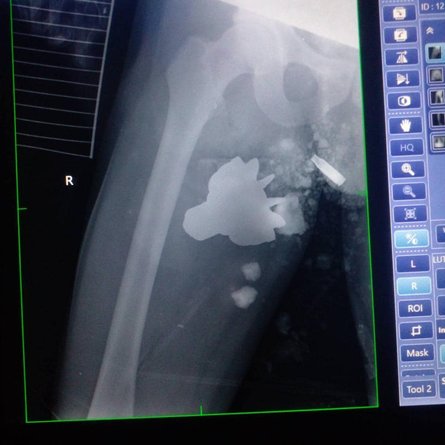

Военные медики вытянули из тела бойца ВСУ хвостовик мины | Фото: Facebook Командования медицинских сил Вооруженных Сил Украины

Во время очень сложной операции, которая происходила в прифронтовом госпитале, из тела раненного украинца врачи достали хвостовик от мины, который мог отобрать жизнь военнослужащего.

Специалисты не только аккуратно обезвредили предмет, но и спасли ногу пострадавшему.

"На этот раз обломок повредил магистральные сосуды конечности. Операционная команда без ущерба для пациента и медицинского коллектива достала хвостовик и спасла конечность. Сейчас самочувствие пациента стабильное. Специалисты Медицинских сил готовят его для дальнейшей эвакуации", — говорится в сообщении.